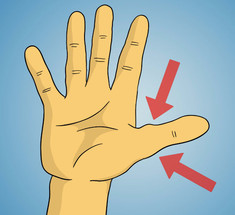

Тревожный симптом: Почему могут исчезнуть белые лунки на ногтях

Экология здоровья: Официальная медицина допускает возможность диагностики заболеваний по состоянию ногтей, лунок в...